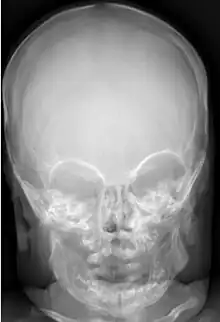

Anteroposterior radiograph of the skull showed massive sclerosis of the skull bone associated with significant cortical hyperostosis and enlargement of the mandible secondary to cortical new bone formation.

Radiographs initially show layers of periosteal new bone formation with cortical thickening. Periosteal new bone may cover the diaphysis of the bone, causing an increase in diameter of the bone. Over time, the periosteal new bone density increases, becoming homogeneous with the underlying cortex. Eventually, the bone remodels and resumes a normal appearance.